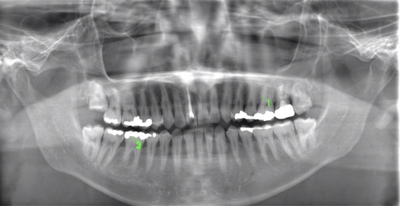

CASE 10

基本情報

| 年齢・性別 | 39歳・男性 |

| 主訴 | 左上下親知らず抜きたい |

| 抜歯期間 | 30分 |

| 抜歯費用 | 約2,500円(保険内) 別途CT撮影で3,000円 (2022年7月現在) |

| 抜歯内容 | 左上下の親知らず抜歯 |

| 治療方針 |

親知らずは抜いたほうが良い認識はあったものの、痛みや腫れが出ることを知って、勇気が出ないままでいたとのことでした。 そのまま放置していたら虫歯になってしまい、今回ご来院されました。しっかりと麻酔をして緊張をほぐしながら抜歯を始めました。完全萌出のため、時間を要することなくすぐに抜歯することができました。 |